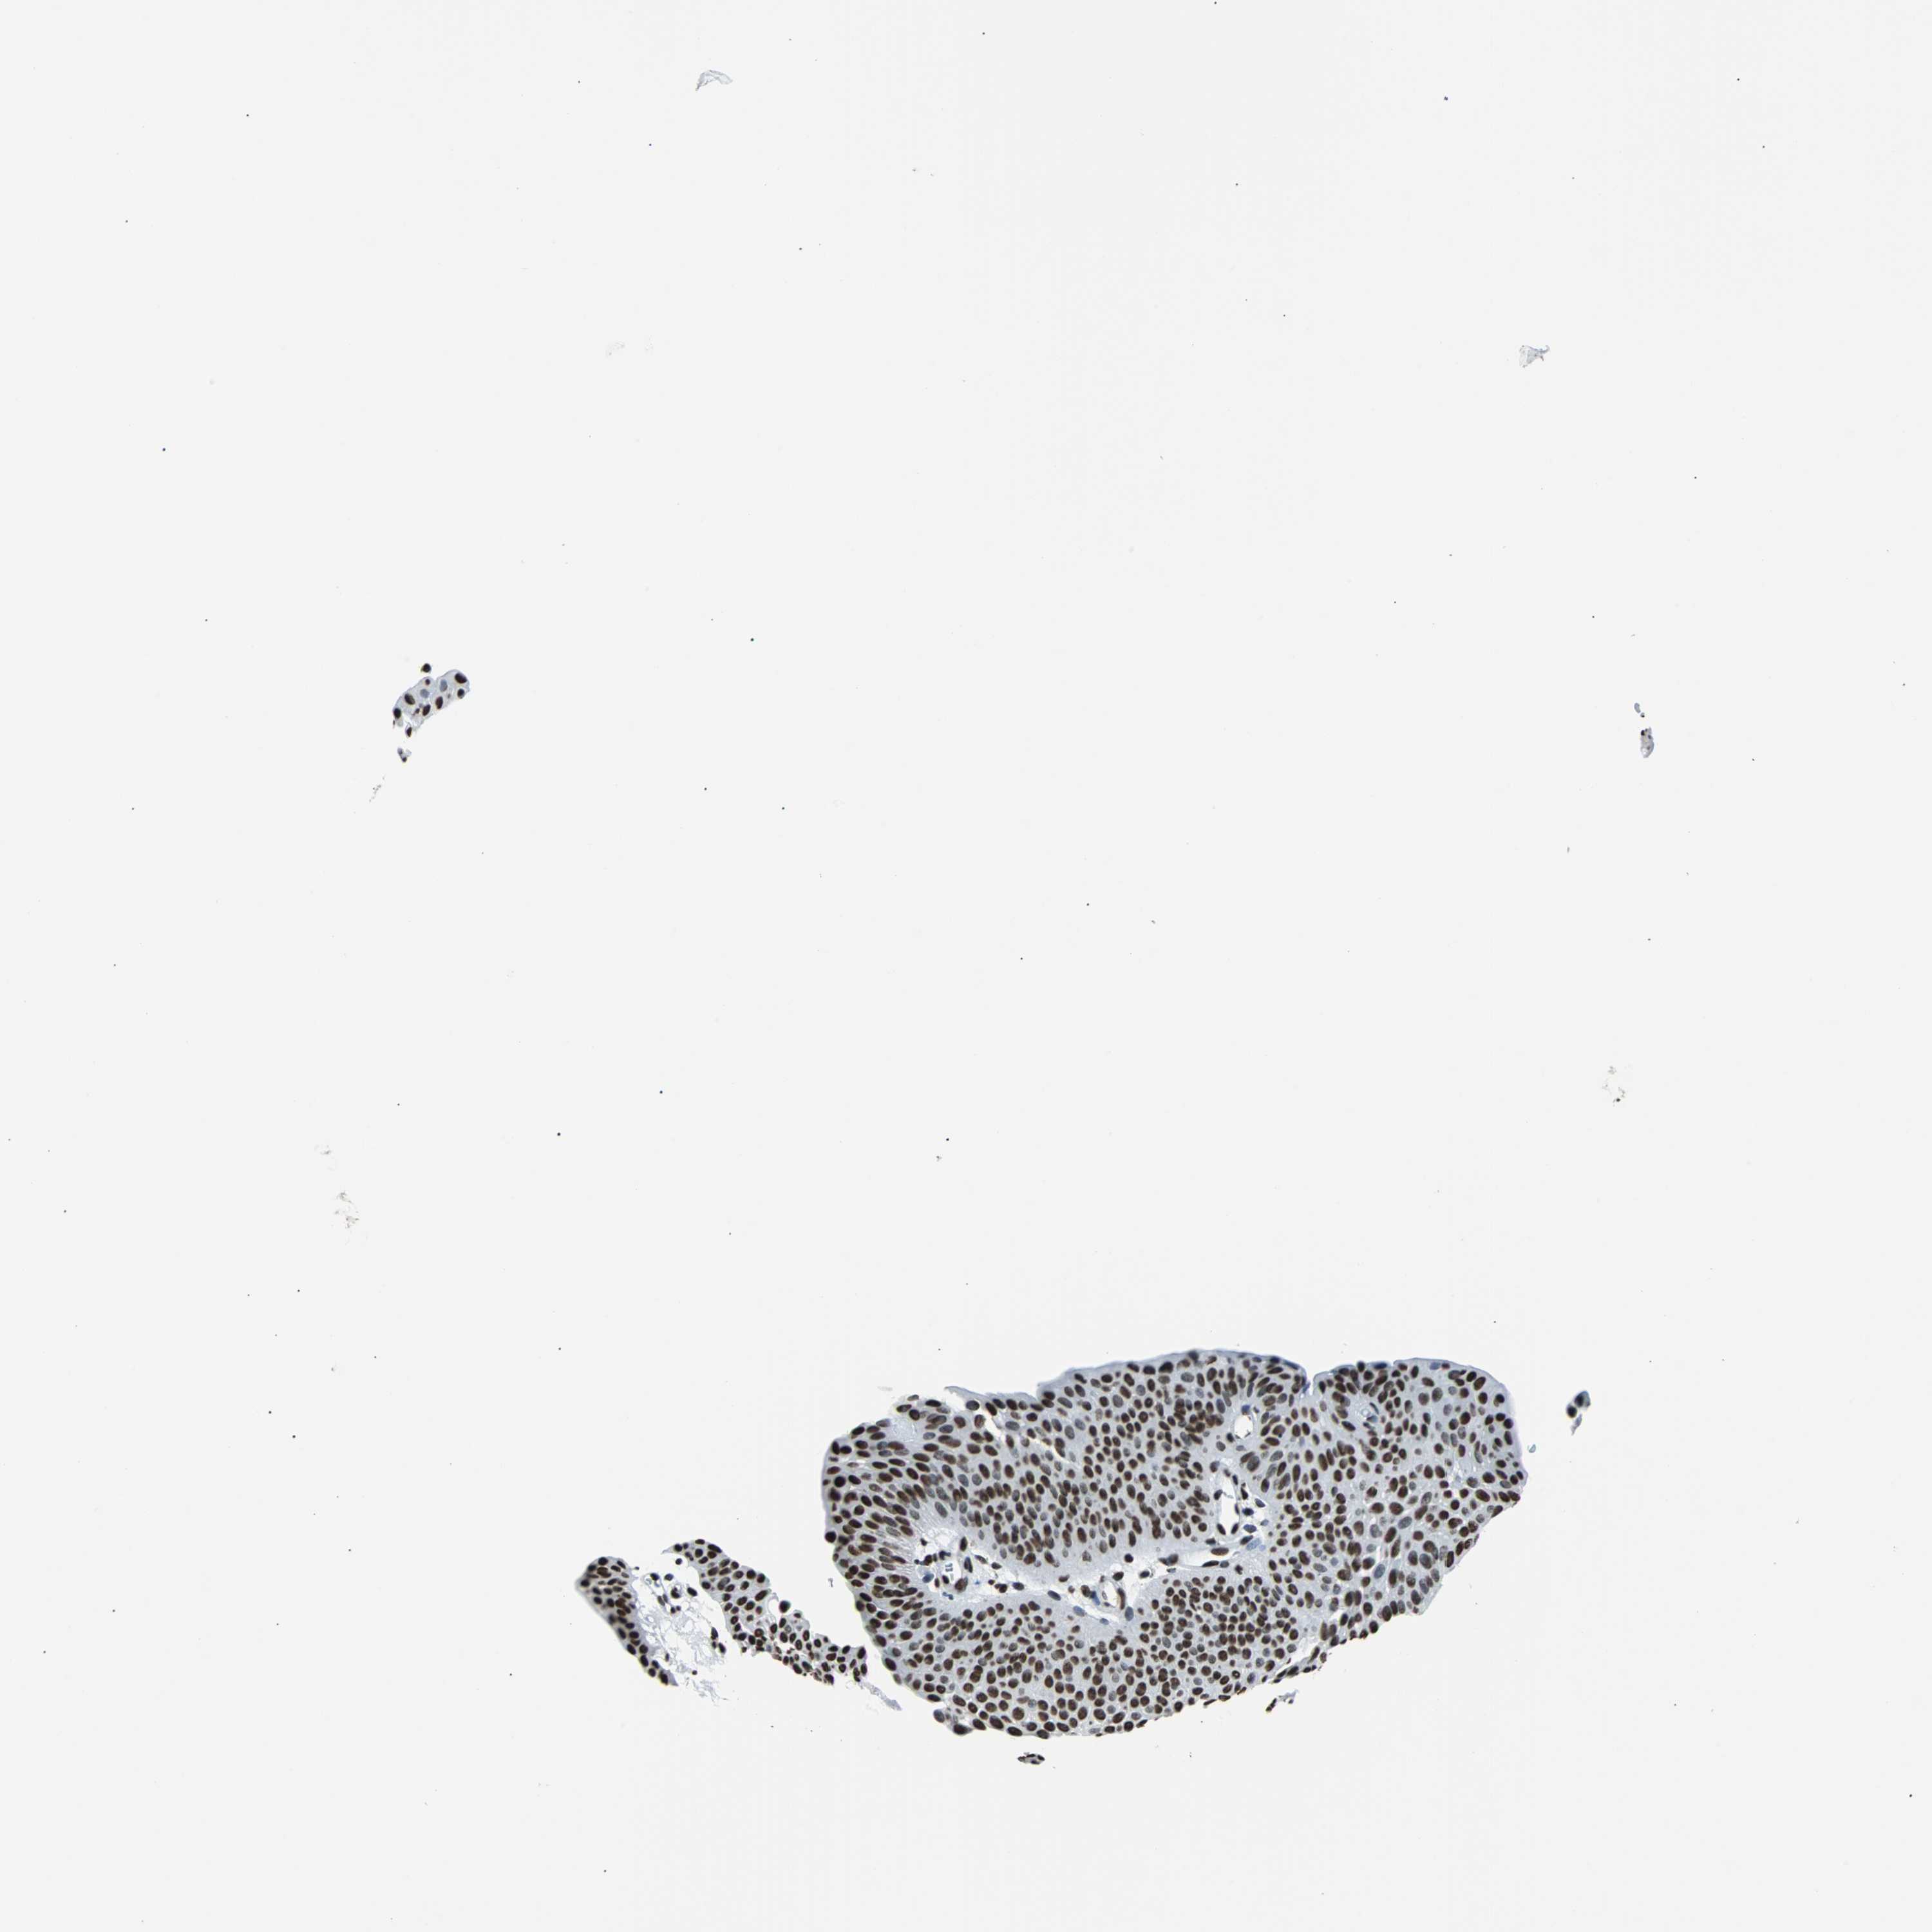

UROTHELIAL CANCER - Protein expressioni

A mouse-over function shows sample information and annotation data. Click on an image to view it in a full screen mode. Samples can be filtered based on level of antibody staining by selecting one or several of the following categories: high, medium, low and not detected. The assay and annotation is described here.

Note that samples used for immunohistochemistry by the Human Protein Atlas do not correspond to samples in the TCGA dataset.

Antibody stainingi

Antibody staining in the annotated cell types in the current human tissue is reported as not detected, low, medium, or high, based on conventional immunohistochemistry profiling in selected tissues. This score is based on the combination of the staining intensity and fraction of stained cells.

Each image is clickable and will lead to virtual microscopy that enables deeper exploration of all samples and also displays staining intensity scores, fraction scores and subcellular localization as well as patient and tissue information for each sample.

Antibody HPA006149

Staining

High

Medium

Low

Not detected

Intensity

Strong

Moderate

Weak

Negative

Quantity

>75%

75%-25%

<25%

None

Location

Nuclear

Cytoplasmic/membranous

Cytoplasmic/membranous,nuclear

Urothelial carcinoma, High grade

Urothelial carcinoma, Low grade